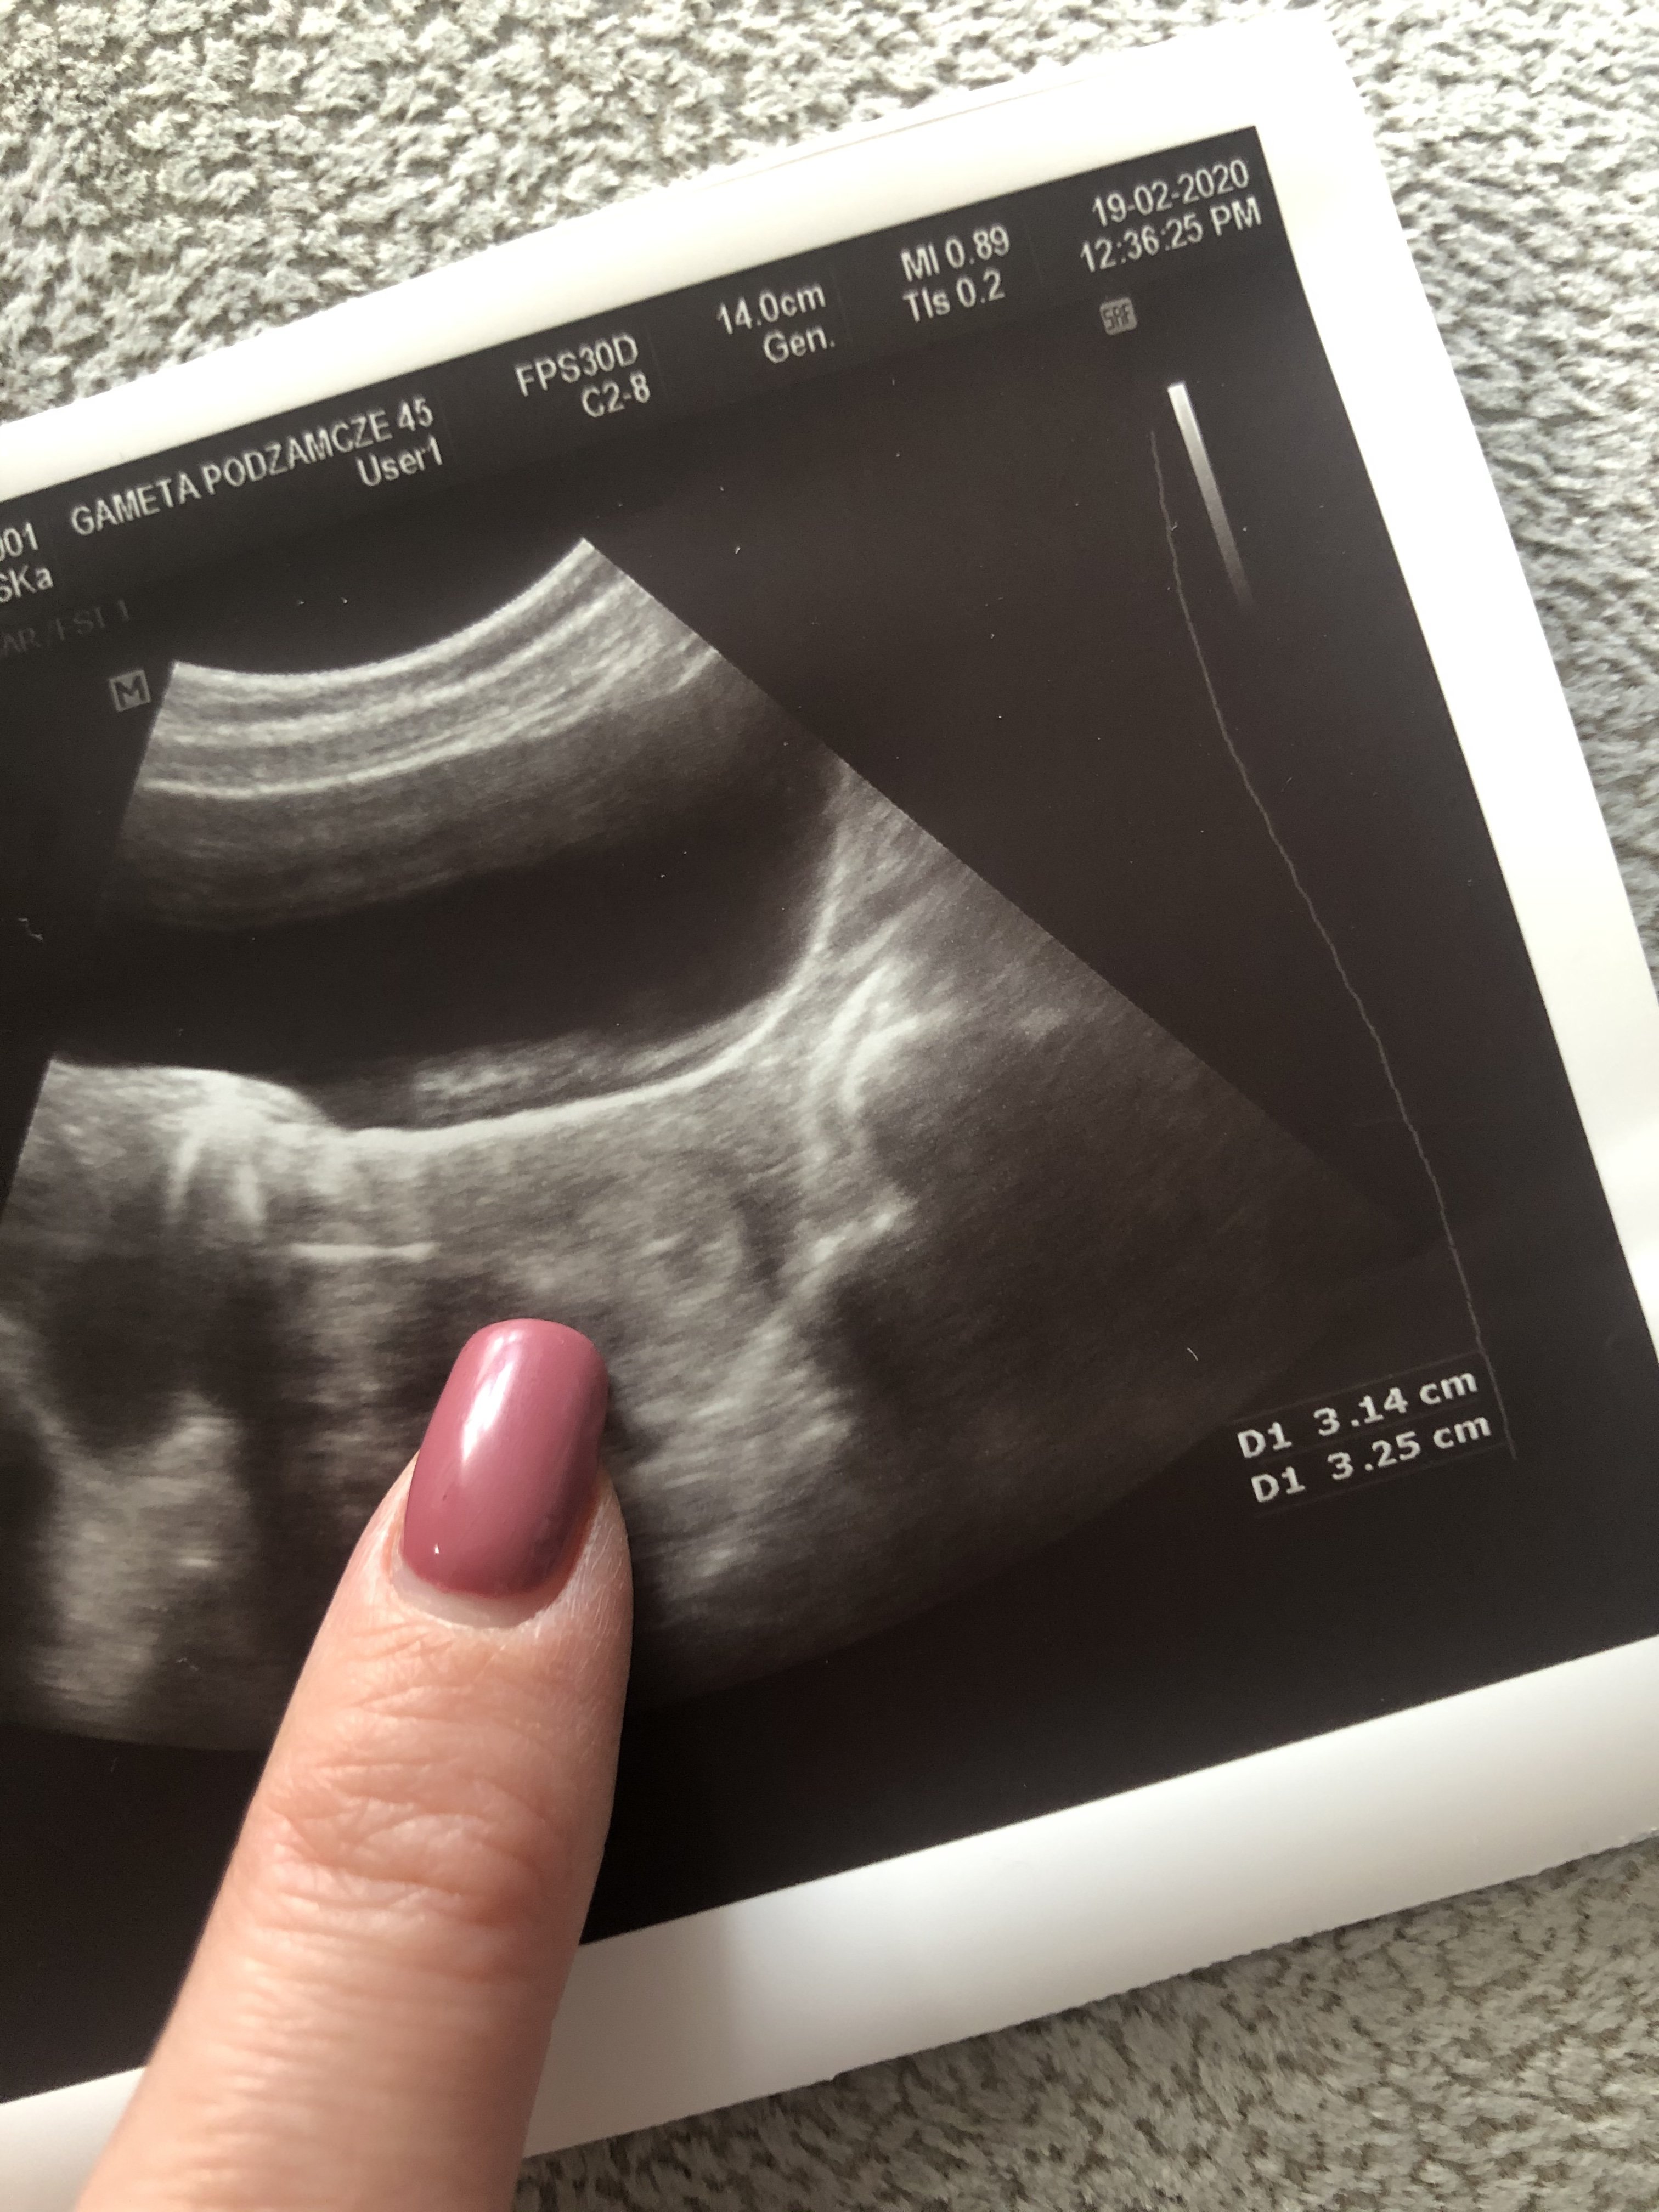

Dodaje Wam zdjęcie usg z transferu i mojej blastki 4AA